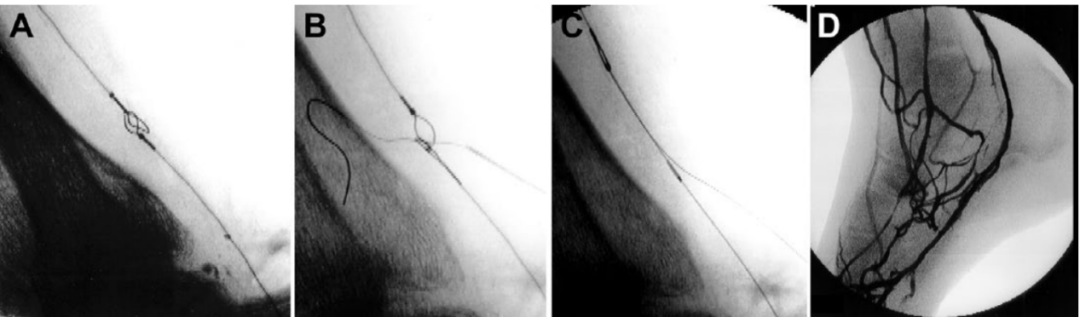

图3. 静脉动脉化简化技术示意图。(A)插入针头,穿过静脉的两层壁和圈套器环。(B)针头到达动脉并刺穿球囊导管。将一根0.018英寸的导丝推进并放置在刺穿的球囊内。(C)撤出球囊导管,保持导丝卡在球囊内,以便回撤通过股鞘将其引出体外。(D)顺行推进支撑导管。(E)推进0.014英寸的导丝,直至其明确位于静脉腔内。(F)动静脉吻合口血管成形术。

图4. 静脉动脉化简化技术术中造影(A) 圈套器和充盈球囊重叠。(B) 22-G微穿刺针经皮推进,穿过球囊和圈套器环。(C) 取出球囊导管,同时保持导丝在其中。(D) 静脉动脉化的血管造影图像。